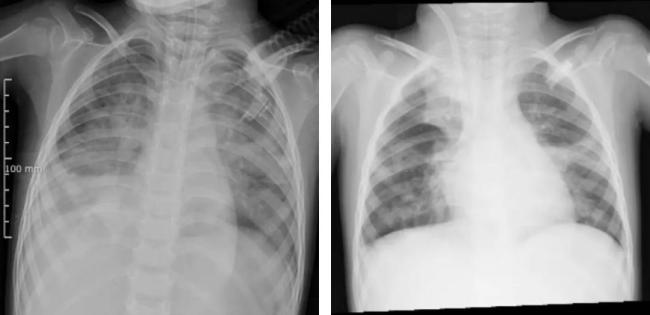

“白肺”通常提示肺部病變較重,可能與重癥肺炎、急性呼吸窘迫綜合征(ARDS)等疾病相關(guān)。大多數(shù)兒童感染流感病毒后表現(xiàn)為發(fā)熱、咳嗽、咽痛、肌肉酸痛等癥狀,通常在一周內(nèi)自愈。少數(shù)患兒可能發(fā)展為肺炎,甚至出現(xiàn)“白肺”。流感病毒感染會削弱呼吸道防御能力,容易繼發(fā)細菌感染,如肺炎鏈球菌、金黃色葡萄球菌、肺炎支原體等,這些細菌或支原體感染可能導(dǎo)致或加重肺炎,嚴重時會出現(xiàn)“白肺”。